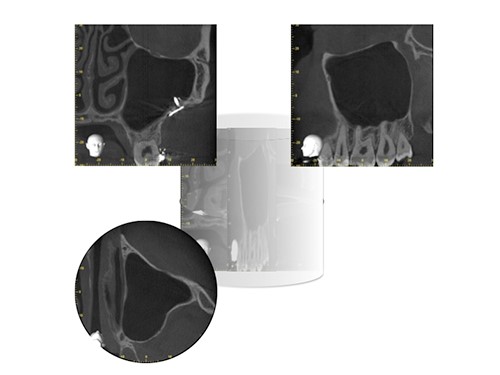

回転に伴い、多数の投影が作成され、これらからデジタルボリュームが生成され、そこから 3 つの相互に垂直な平面で画像が再構成されます。軸方向、冠状方向(前頭方向)、矢状方向(図2)。

図2. CBCTボリュームデータから軸方向、正面、矢状方向の画像を再構成